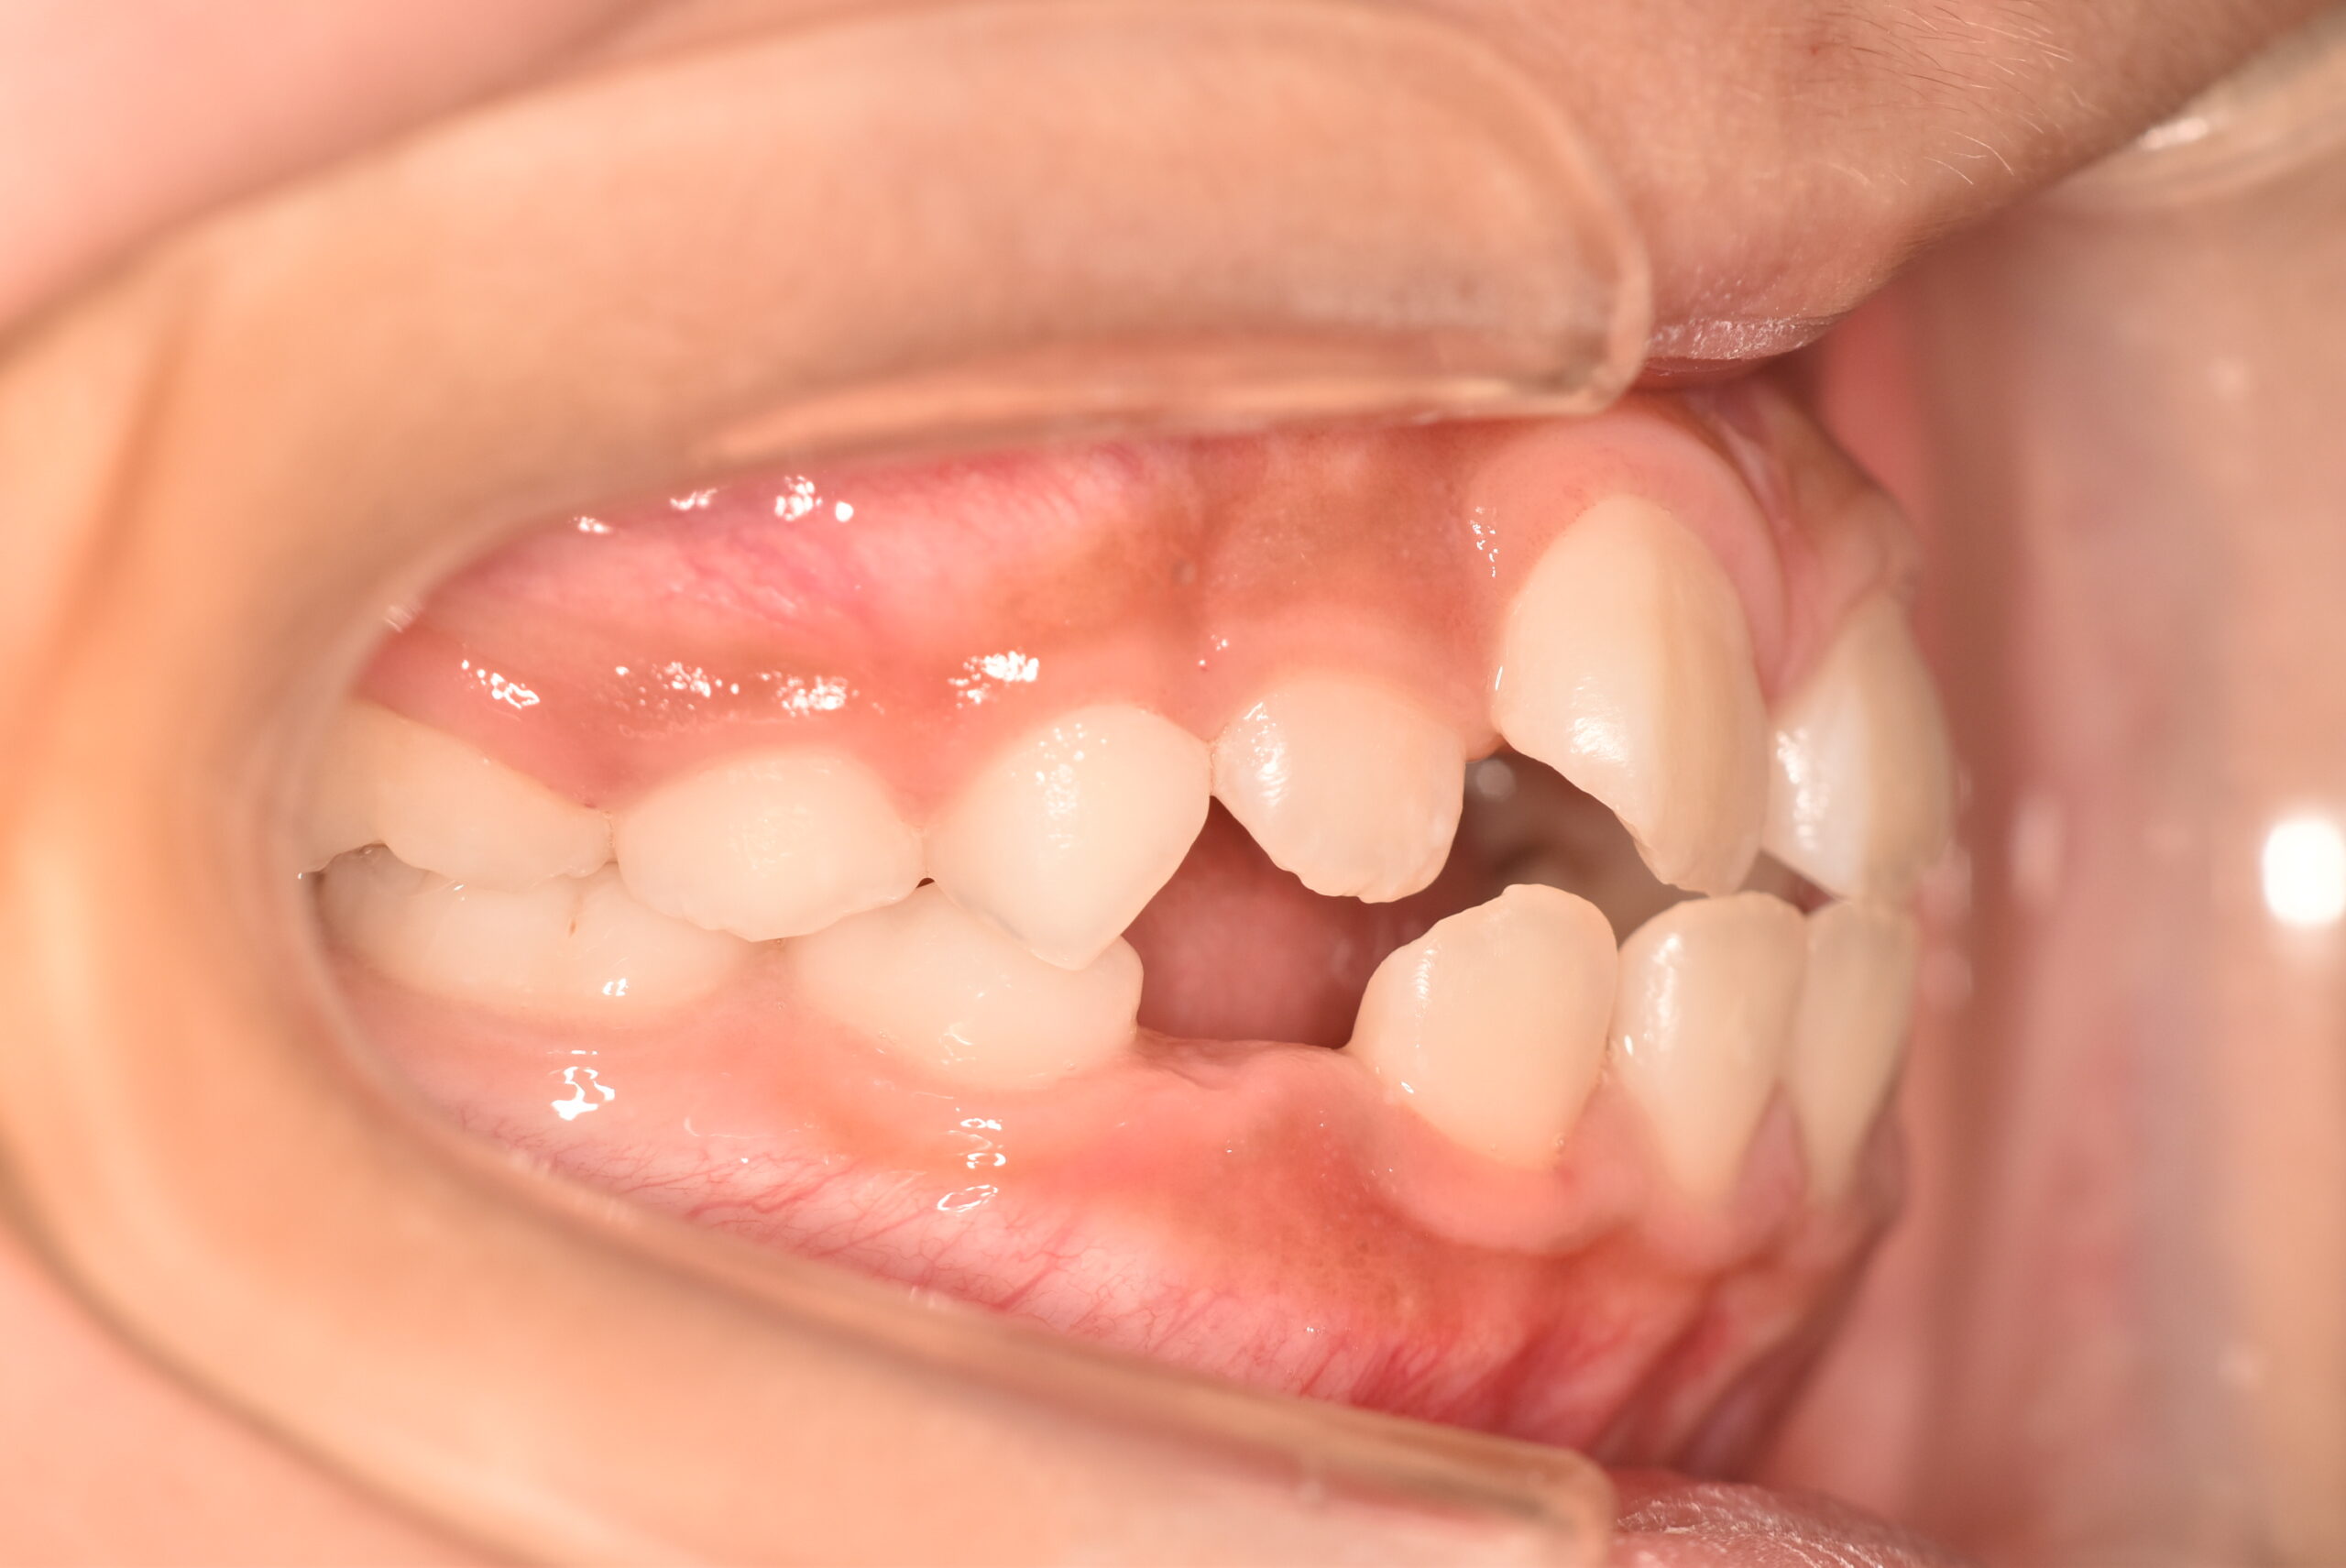

初診時

症例 症例 症例 症例

動的治療終了時

年齢

9歳 性 別 女性

治療期間 7ヶ月 費 用 矯正施術料:750,000円

調整料:4,000円/月

治療内容の詳細 初診時9歳の女児で、歯のがたつきを気にされ来院されました。

検査の結果、前歯部叢生を伴うアングルⅠ級不正咬合と診断しました。

治療としてはマウスピース矯正(インビザラインファースト)で配列を行い、上下顎の側方拡大と萌出スペースを確保しました。

治療期間は、7ヶ月でした。

今後、側方歯生え変わりまで経過観察を行います。